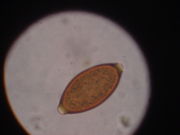

The human whipworm (Trichuris trichiura or Trichocephalus trichiuris), is a roundworm, which causes trichuriasis when it infects a human large intestine. The name whipworm refers to the shape of the worm; they look like whips with wider "handles" at the posterior end.

Infection occurs through accidental ingestion of eggs (which are usually found in dry goods such as beans, rice, and various grains) and is more common in warmer areas. The eggs hatch in the small intestine, and then move into the wall of the small intestine and develop. On reaching adulthood, the thinner end (the front of the worm) burrows into the large intestine and the thicker end hangs into the lumen and mates with nearby worms. The females can grow to 50 mm (2 inches) long. Neither the male nor the female has much of a visible tail past the anus.